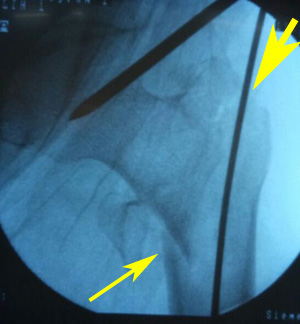

Case 3

A 40-year old male was injured in a road side accident resulting in intertrochanteric fracture of the left femur (AO/OTA 31-A3.1). The patient was submitted to osteosynthesis with PFN. Immediate post-operative radiograph of the patient revealed acceptable NSA, acceptable position and size of screws, restoration of alignment, but not maintaining anterior bony contact. At 3 months post-operative, the patient presented with lateral migration of the lag screw, with the derotation screw maintaining its original position (Z-effect). Patient was kept on strict follow-up, so that any chance of failure of fixation can be detected. At 7 months, patient showed clinico-radiological signs of union. Although, the lag screw moved laterally, but it was still well positioned with regard to the tip apex distance and the fracture was adequately aligned, hence no failure in osteosynthesis occurred. Radiographic images of the patient are presented in Figure 8.

Figure 8b Immediate post-operative radiograph showing restoration of NSA & medial buttress. Also note the acceptable position & size of screws. Arrow in lateral projection showing lack of anterior bony contact.

Figure 8c Three months post-operative radiograph showing lateral migration of the lag screw, with the derotation screw maintaining its original position (Z-effect).